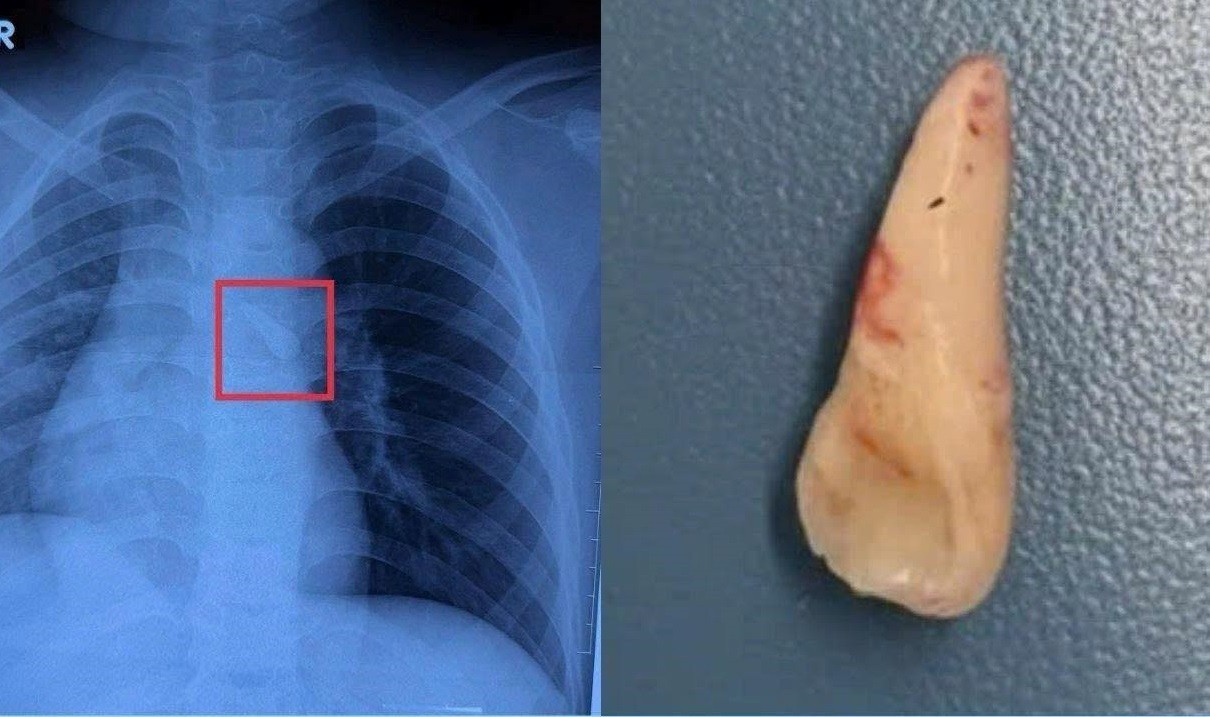

Theo khai thác bệnh sử, thời điểm xảy ra tai nạn, bé không đội mũ bảo hiểm. Khi tai nạn xảy ra, trẻ bị va đập vùng đầu nhưng không mất ý thức. Trẻ được sơ cứu tại bệnh viện địa phương rồi chuyển đến Bệnh viện Nhi Đồng 1 để tiếp tục theo dõi. Trên kết quả chụp X-quang bác sĩ phát hiện một dị vật cản quang nằm trong khí quản, đặt ra nguy cơ tắc nghẽn đường thở nếu không xử trí kịp thời.

Chiếc răng bị gãy rơi vào đường thở của trẻ sau tai nạn được các bác sĩ lấy ra ngoài qua nội soi

BS Lý Phạm Hoàng Vinh, khoa Tai Mũi Họng, Bệnh viện Nhi Đồng 1, cho biết thăm khám lâm sàng kết hợp hình ảnh học ghi nhận bệnh nhi bị mất răng số 21. Từ chi tiết này, các bác sĩ nghĩ nhiều đến khả năng chiếc răng đã bị hít sặc vào đường thở trong lúc tai nạn nhưng không được phát hiện ngay. Kết quả kiểm tra tổng thể cho thấy, bệnh nhi bị vỡ xương sàn ổ mắt, đụng dập nhãn cầu, dị vật đường thở, chấn thương đầu và vết thương vùng đầu do tai nạn giao thông.

Trước nguy cơ biến chứng hô hấp nghiêm trọng, bệnh viện đã tổ chức hội chẩn liên chuyên khoa. Các bác sĩ quyết định nội soi đường thở khẩn, lấy thành công chiếc răng nằm trong khí quản của bệnh nhi. Theo BS Hoàng Vinh, các tai nạn gây chấn thương hàm mặt, răng gãy rất dễ bị hít vào đường thở mà triệu chứng ban đầu không rầm rộ nên dễ bỏ sót. Vì vậy, khi trẻ gặp tai nạn giao thông, dù còn tỉnh táo và triệu chứng nhẹ, vẫn cần được thăm khám đầy đủ tại cơ sở y tế có chuyên khoa.